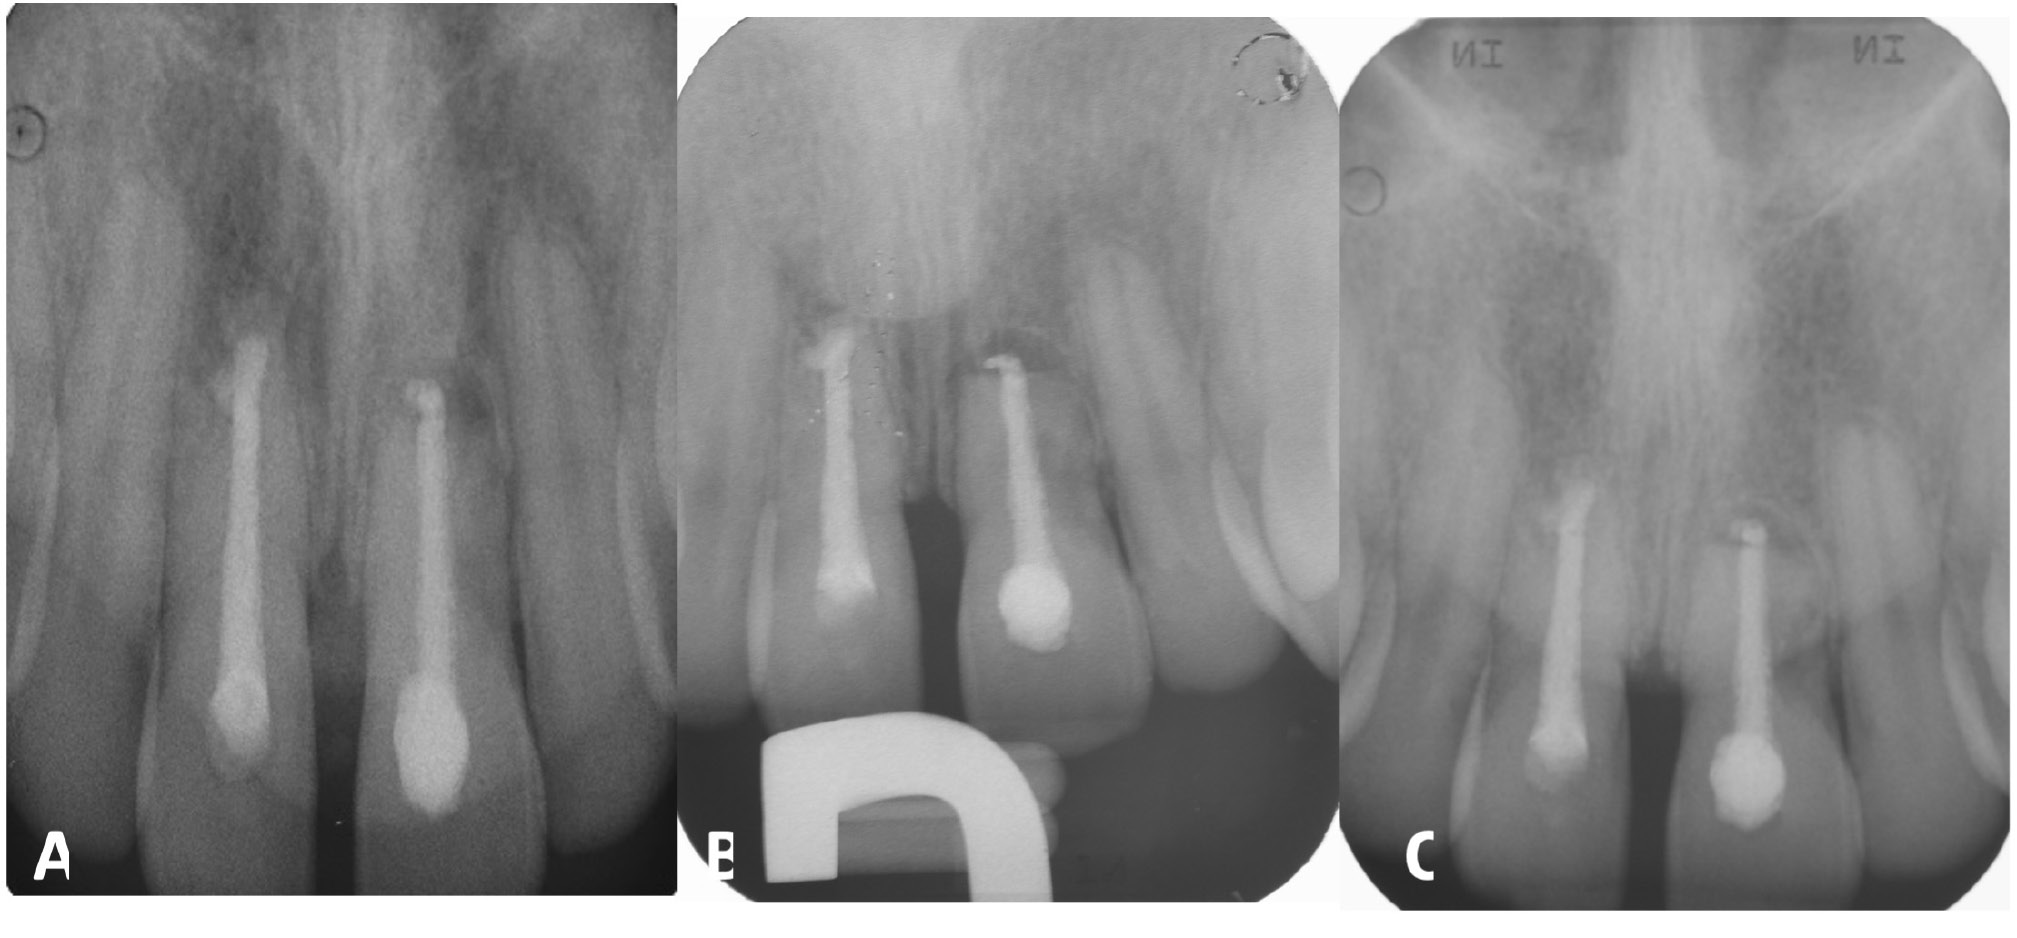

The inflammatory reaction that results in no healing is caused by the infection of the root canal system. In cases of root fracture, the infection occurs at the fracture site rather than in the periapical tissues. The coronal fragment has a “new apical foramen,” which is now situated at the fracture line rather than at the apical end of the root. Root canal therapy of the coronal fragment can be initiated and calcium hydroxide intracanal medication can be administered. If symptoms persist (i.e., abscess episodes and/or mucous fistula), an apicoectomy can be performed. Figure 4 shows the fractured apical root fragment being removed and retrograde closure of the new root apex,25 which in one case is at the apicectomy level #11 and in the other at the root fracture line #21.26, 27

Figure 13 and Figure 14 show periapical radiographs at 6 months after the 1st (Figure 13) and 2nd apicoectomy (Figure 14A) and at 24 (Figure 14B) and 30 months (Figure 14C) after the trauma, with complete remission of clinical and radiographic symptoms.33